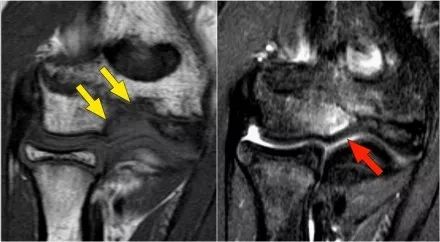

外翻过度综合征的关节病由于外翻过载,在肱骨-尺骨关节的后内侧部分存在剪切力。注意在T1W图像上看到的软骨下硬化(红色箭头)。在T2W图像上存在软骨下骨髓水肿和软骨损失(黄色箭头)。

下图是20岁棒球投手的图像。

冠状图像上有一个美丽的UCL前束,但注意到关节内侧部分有骨赘形成(红色箭头)。当我们按照顺序向下看,可以看到存在一小部分低信号强度(黄色箭头),这是UCL的一部分撕裂。